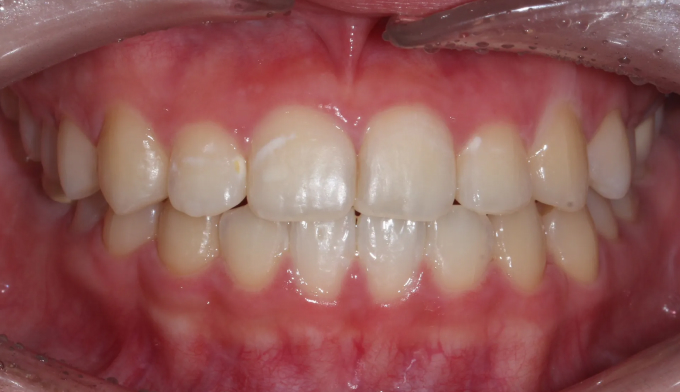

앞니 하나만 뒤로 들어간 경우, 해당 치아만 앞으로 빼내면 되는 간단한 교정이라고 생각하기 쉽습니다.

하지만 해당 치아가 뒤로 들어가면서 전체적인 치열이 한쪽으로 쏠리는 비대칭이 나타났기 때문에 이를 모두 해결하기 위해서는 전체교정을 통한 긴 치료기간이 필요합니다.

안쪽으로 들어간 앞니 양쪽으로 치열을 밀어서 공간을 확보해주고 앞니를 재위치 시켰습니다.

추가로 한쪽으로 틀어진 치열들도 위아래 중심선을 맞추어주었습니다.

총 치료기간은 17개월입니다.